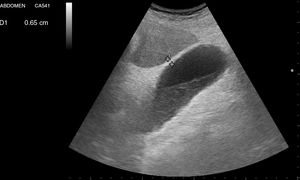

La vía biliar (colédoco) se localiza en un corte oblicuo, paralela y por delante de la porta, junto a la arteria hepática (presentan grosores similares y el Doppler puede ayudar a diferenciarlas). Si se gira el transductor 90° se visualizarán estas estructuras transversalmente (imagen del «ratón Mickey») (fig. 6). El calibre del colédoco debe ser < 6mm, excepto en pacientes colecistectomizados (< 10mm). Los conductos biliares intrahepáticos no se ven en condiciones normales. La vesícula biliar tiene forma ovalada (aunque variable20), sin ecos en su interior, < 4-5cm de diámetro transversal (el más fiable) y < 10cm de diámetro longitudinal. La posición del fondo es variable, por lo que se deben hacer diferentes cortes oblicuos hasta conseguir un corte longitudinal de la vesícula.